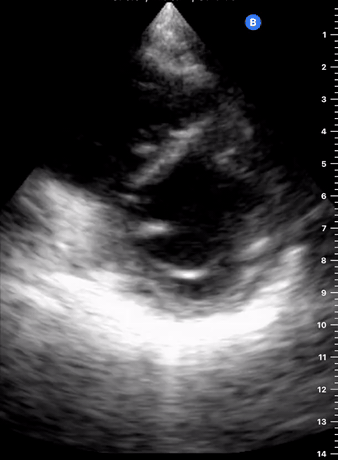

As the transverse (short-axis) images show the relative wall thickness and contractility, this view is the best for assessing regional wall motion. Also, the inferior portion of the view (papillary muscles) is ideal for comparing the relative size of both ventricles. In expert hands, the superior portion of the view allows evaluation of the aortic valve and RV overload.

A good PSAX starts from a proper parasternal long-axis. Without sliding or displacing the probe, rotate it 90º clockwise so the marking points to the left shoulder. The resulting image is a transverse cut to the heart’s long axis, hence, a short-axis view.

While maintaining the short axis, sweep or gently fan the probe along the long axis to obtain a series of ‘sectional’ views of the LV and RV.